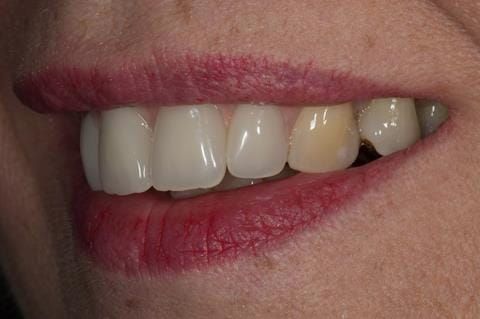

- Extract the upper 2-2 teeth and replace with an interim acrylic based partial denture. Reline the interim denture over 9 - 12 months, replacing with a definitive cobalt chromium based partial denture. The definitive denture would ideally be designed as an occlusal protective splint to reduce the the potential for mechanical wear and breakages of the moderately/heavily restored maxillary dentition. In addition, should further upper teeth require extraction they could be added on to the denture cobalt chromium framework - therefore a new prosthesis would not be required as future teeth are lost. This option would produce an excellent aesthetic outcome. This is the option the patient chose to have.

Following consultation and second discussion appointment the patient chose to have option 3 namely, a maxillary cobalt chromium based partial denture/protective occlusal splint. The clinical situation and treatment process is shown in detail below with photographs. The patient was successfully rehabilitated with this and her quality of life considerably improved. The clinical work was provided by Finlay and the technical work by Rowan.